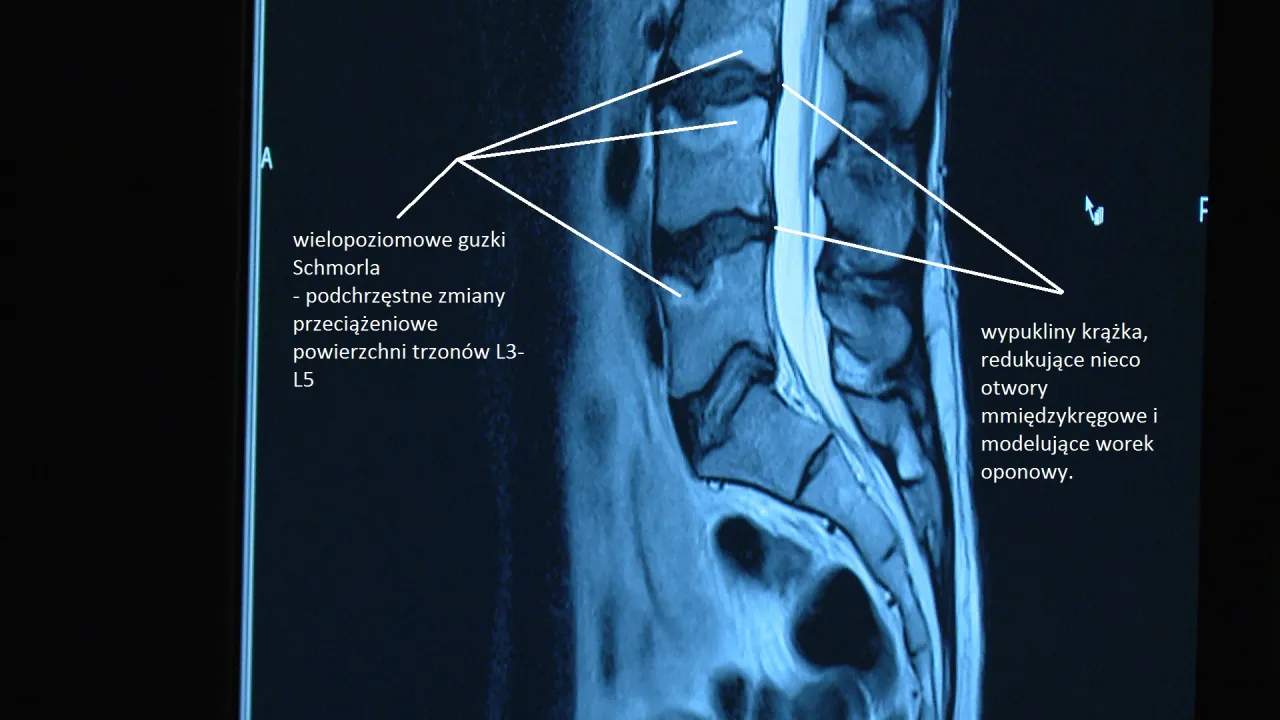

Zmiany zwyrodnieniowe kręgosłupa: Z wiekiem nasz kręgosłup naturalnie się zużywa. Procesy zwyrodnieniowe, takie jak dyskopatia (potocznie nazywana "wypadnięciem dysku", choć dysk tak naprawdę "wypada" rzadko, częściej dochodzi do jego uwypuklenia lub przepukliny) czy stenoza kanału kręgowego (zwężenie kanału, przez który przechodzi rdzeń kręgowy i nerwy), są częścią tego procesu. Niestety, siedzący tryb życia, brak ruchu i nadwaga mogą znacząco przyspieszać te zmiany, prowadząc do bólu i ograniczenia ruchomości.

- RTG (rentgen): Pozwala ocenić strukturę kostną kręgosłupa, wykryć zmiany zwyrodnieniowe, wady postawy czy złamania.

- Rezonans magnetyczny (MRI): To badanie daje znacznie bardziej szczegółowy obraz tkanek miękkich dysków, nerwów, rdzenia kręgowego. Jest kluczowe w diagnostyce dyskopatii, rwy kulszowej, stanów zapalnych czy nowotworów.